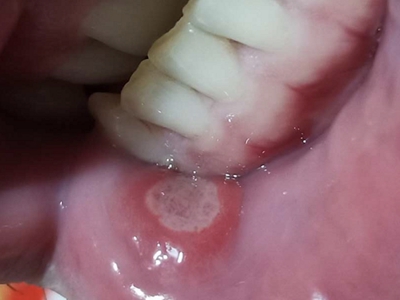

口腔溃疡为圆形或椭圆形,直径0.2-0.5cm,溃疡单个或由数个连成一片,溃疡表浅边缘整齐,外观呈灰黄色或灰白色,上覆盖黄白渗出膜,周围黏膜充血、水肿而有红晕。

皮损局部有烧灼样疼痛,于进餐时加重,影响进食、说话。严重溃疡直径可达1-3cm,深及黏膜下层甚至肌肉。

口腔溃疡的早期黏膜上皮细胞水肿,随后炎症细胞大量浸润,上皮溶解破溃脱落,形成溃疡。